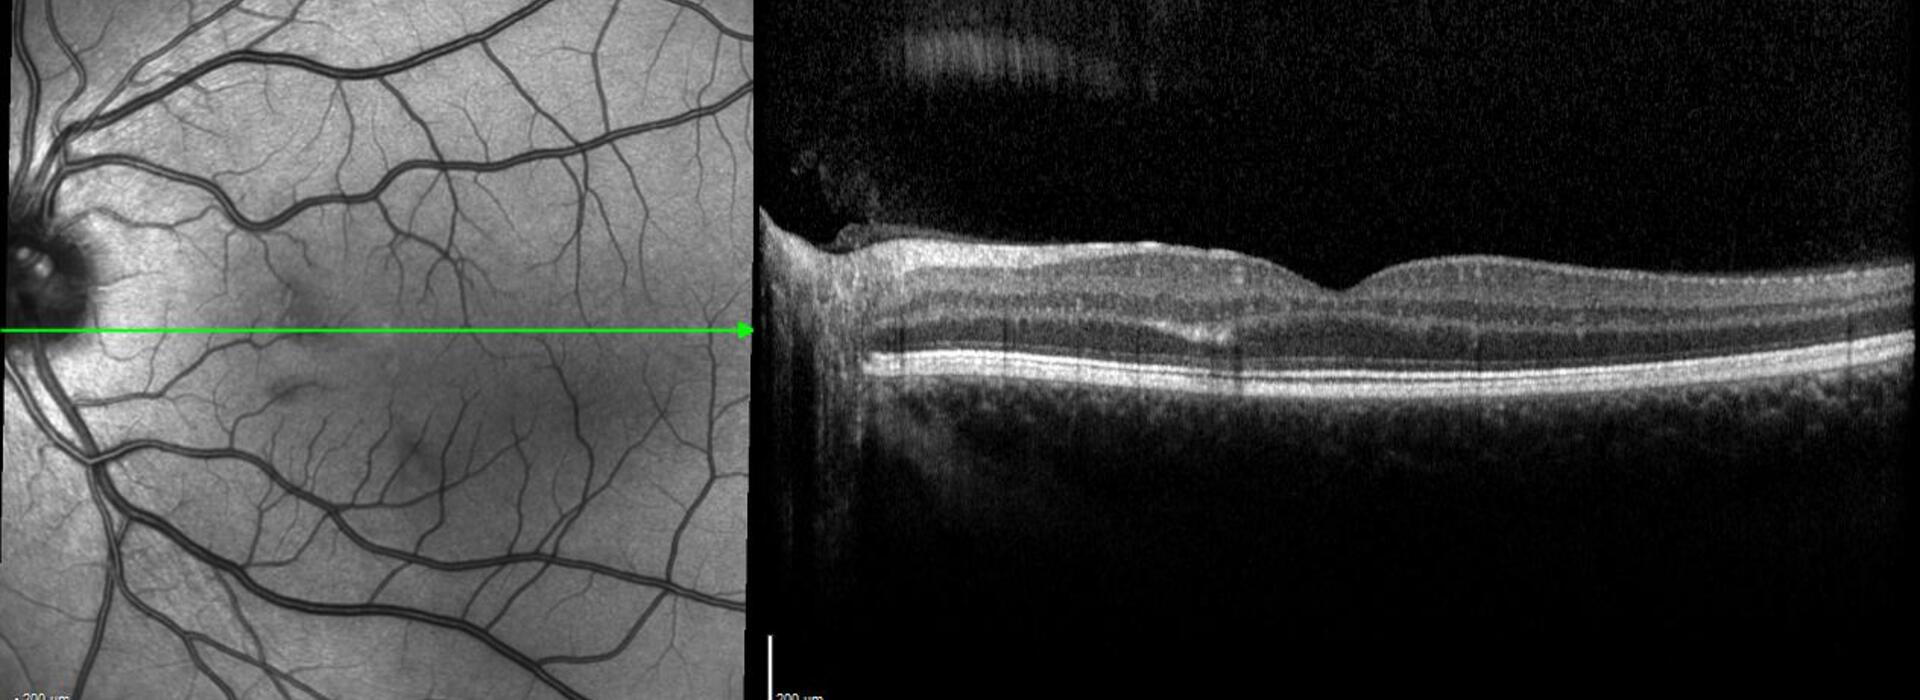

El Dr Pedro Fernández revisa los principales signos clínicos y estructurales de las uveítis posteriores, resaltando el papel esencial de la imagen multimodal para localizar la inflamación, determinar su grado y severidad, evaluar la actividad del proceso y detectar de forma precoz posibles complicaciones. Esta información es crucial no solo para el diagnóstico y seguimiento oftalmológico, sino también para orientar adecuadamente el tratamiento sistémico en conjunto con reumatología y medicina interna.

Signos clave en uveítis posteriores